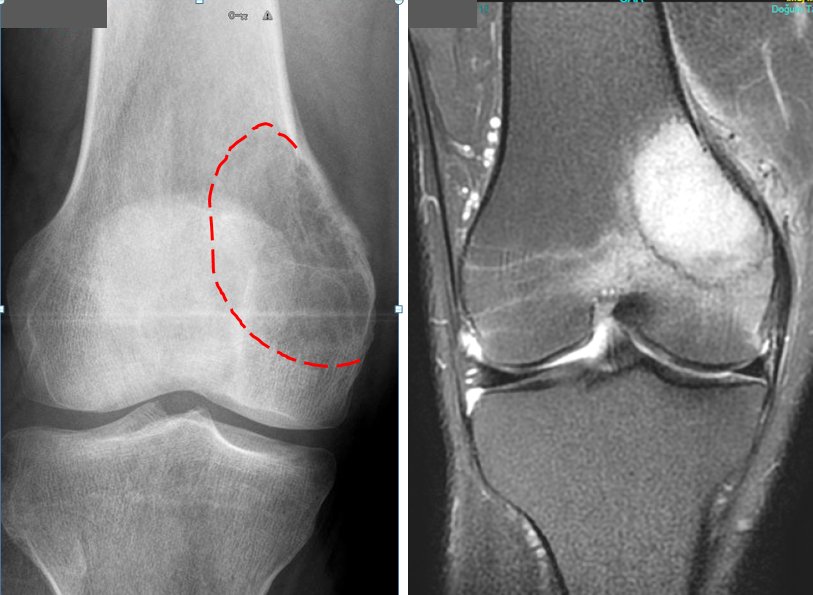

Pic 10

Pic 11

Pic 12

Giant cell bone tumor is also more common in young people. Although this type of tumor is mostly seen in the knee, it occurs in all parts of the body, especially in the joint areas (picture-10). It is usually in the form of blunt pain felt in the last few months. It can only be treated with surgery. The tumor is completely removed from the bone and the cavity is filled with bone cement or bone powders (pic-11). If the removal of the tumor is not done completely, recurrence is inevitable.